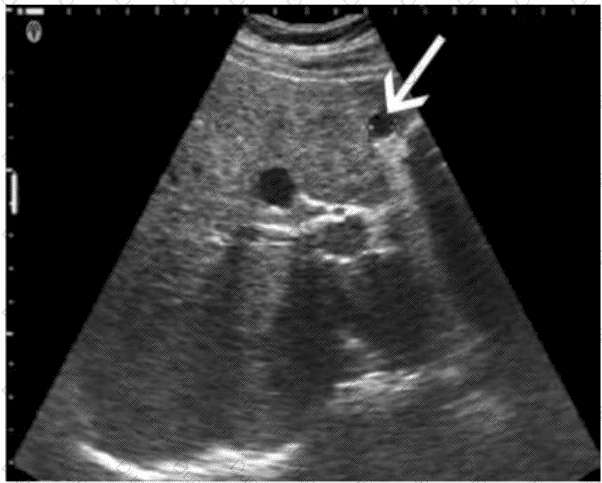

Which condition is most consistent with the sonographic appearance indicated by the arrows on this image obtained post thyroidectomy?

AB-Abdomen Question 6

Options:

A.

Recurring papillary thyroid cancer

B.

Normal postsurgical lymph node

C.

Residual glandular tissue

D.

Reactive lymph node

Buy Now